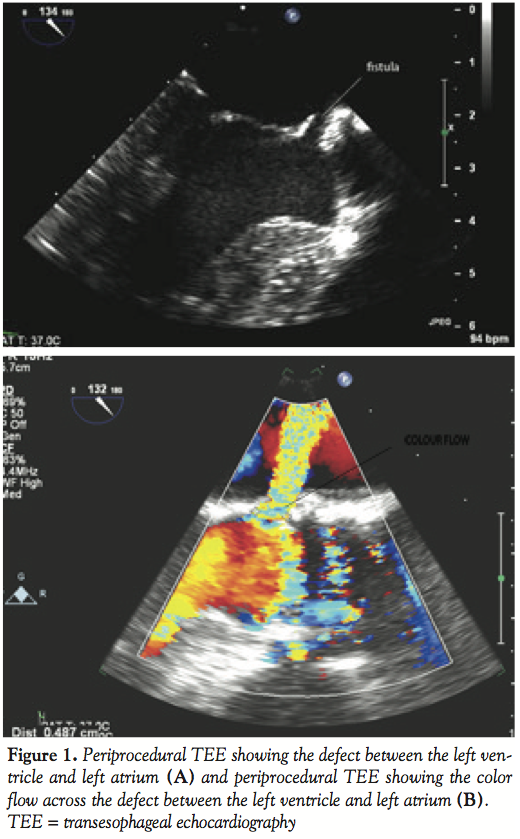

Periprocedural TEE showed the defect between the LV and the LA measured 7 mm (Figures 1A and B) and 2 color flow jets were visualized suggesting 2 leaks adjacent to each other. The defect was also clearly visualized on 3D TEE (Figure 2). TEE guidance is very useful in this situation to assess the anatomy clearly and guide device closure percutaneously.